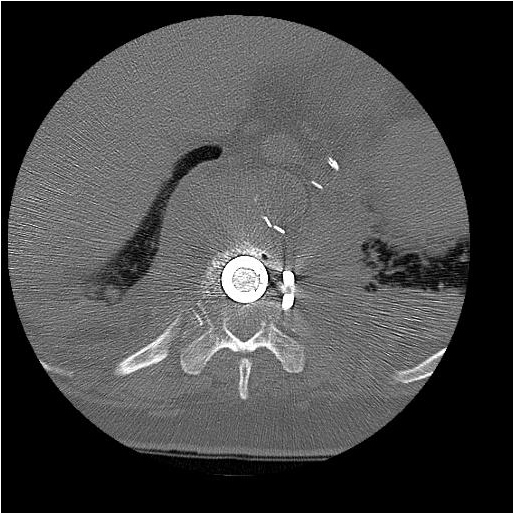

The thoracic spine can be approached through the right or left chest and communication with the spine surgeon is mandatory so that the approach and extent of exposure can be tailored appropriately. In the absence of lateralizing pathology, either a right or left-sided thoracotomy can be used to expose the thoracic spine. As a general rule, the upper thoracic spine (T2-9) is better approached from the right side because of the location of the heart, aortic arch and great vessels. Conversely, in the case of the thoracolumbar spine (T10-L2) a left-sided thoracotomy is preferred to avoid liver retraction. The side of approach must provide maximum exposure to the pathology to be treated. Local factors such as previous thoracotomy, pleurodesis, or infection should also be considered. In general, a right sided approach provides more direct access to the spine, as the mediastinal structures lie to the left of the vertebral bodies. CT and MRI allow for a precise evaluation of the anatomy of the spine pathology and the related intra-thoracic structures (Figures 1a, 1b).